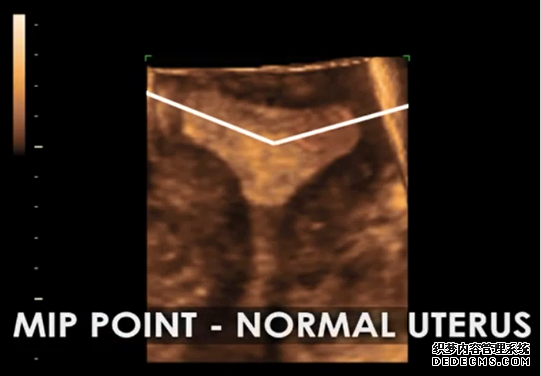

完美的最佳植入点定位技术。利用最新型的3D-4D辅助彩超技术,笙笙试管中心可以完美捕捉正常子宫、畸形子宫的最佳植入位点,为完美着床和完美受孕做好技术保障。